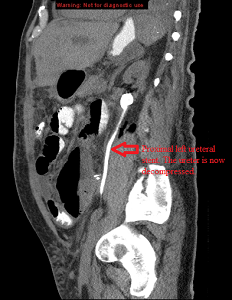

Sagittal CAP post left ureteral stenting

Sagittal CT abdomen and pelvis after left ureteral insertion showing a decompressed collecting system